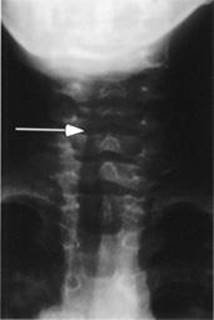

Steeple sign—narrowing of tracheal air column just below the vocal cords (see Figure 12-1).

FIGURE 12-1. Radiograph demonstrating steeple sign of croup.

Note narrowing of airway (arrow). (Courtesy of Dr. Gregory J. Schears.)